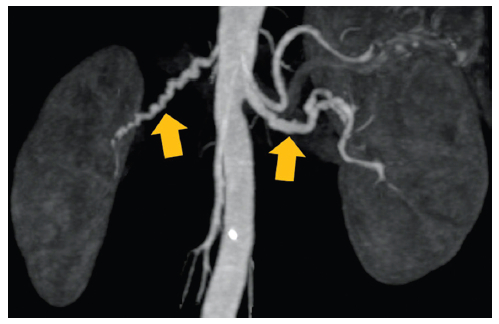

Es un enfermedad idiopática, segmentaria, no inflamatoria y no ateroesclerótica que puede afectar todas las capas de arterias de mediano y pequeño calibre15. Se observa dilatación y estenosis alternadas de los vasos, dando un aspecto arrosariado (Fig. 10). Otras alteraciones menos frecuentes son la disección arterial, ectasia, aneurismas y hemorragia subaracnoidea. Dado que frecuentemente se ven afectados los vasos cervicales y renales, el hallazgo de esta entidad en uno de ellos debe motivar el estudio del otro16.

Displasia fibromuscular. Mujer de 28 años con hipertensión arterial de diagnóstico reciente. TC de abdomen y pelvis con contraste fase angiográfica reconstrucción coronal con máxima intensidad de proyección. Las arterias renales presentan zonas dilatadas y estenóticas que determinan una configuración arrosariada.

Figura 10